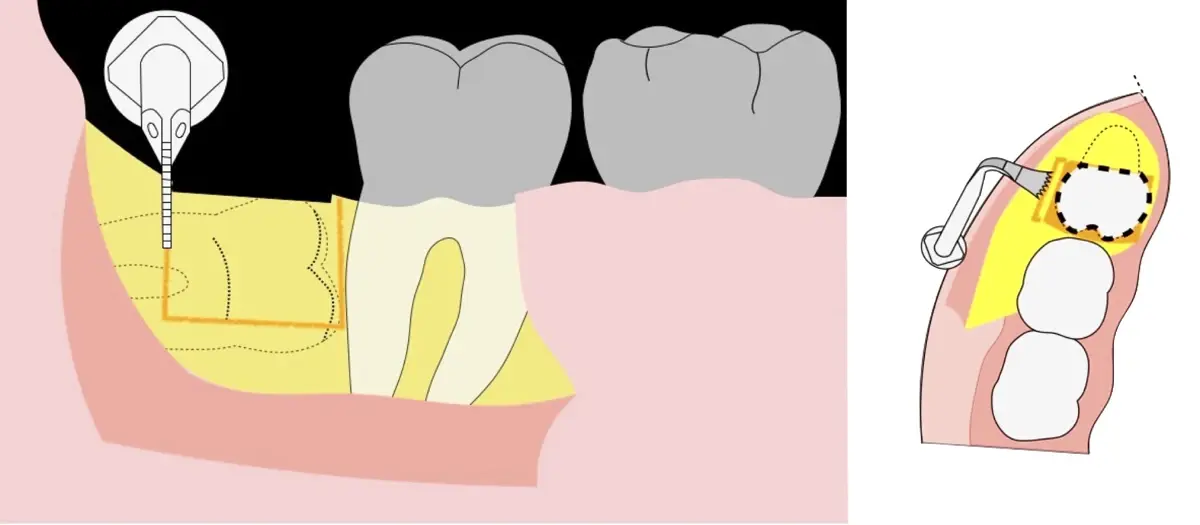

El procedimiento puede variar en su complejidad dependiendo de su ubicación, profundidad, angulación, y la densidad ósea circundante.2 Uno de los pasos más críticos y cruciales en la extracción es la osteotomía previa y concomitante al acceso quirúrgico del diente, para lo cual se utilizan diversos instrumentos como cinceles y martillos, instrumental rotatorio o de corte por ultrasonido.3

En contraste, el instrumento piezoeléctrico utiliza un corte micrométrico que retira un área de superficie mínima de hueso, y reduce el riesgo de termonecrosis marginal en comparación con las fresas rotatorias convencionales.9 Los micromovimientos mejoran la precisión en el corte y el control táctil, y eliminan las macrovibraciones que se producen con los instrumentos rotatorios.10 Su frecuencia de oscilación es la amplitud de 60-200 μm horizontalmente y de 20-60 μm en sentido vertical, lo que es muy inferior en comparación con las micro sierras oscilantes; por lo tanto, proporciona cortes de osteotomía precisos y seguros. Adicionalmente, posee vibraciones ultrasónicas que descomponen el líquido de irrigación en partículas muy pequeñas (fenómeno de cavitación, que produce un efecto hemostático y así reduce la pérdida de sangre), lo que proporciona una visión clara y sin obstáculos del campo quirúrgico11,12.